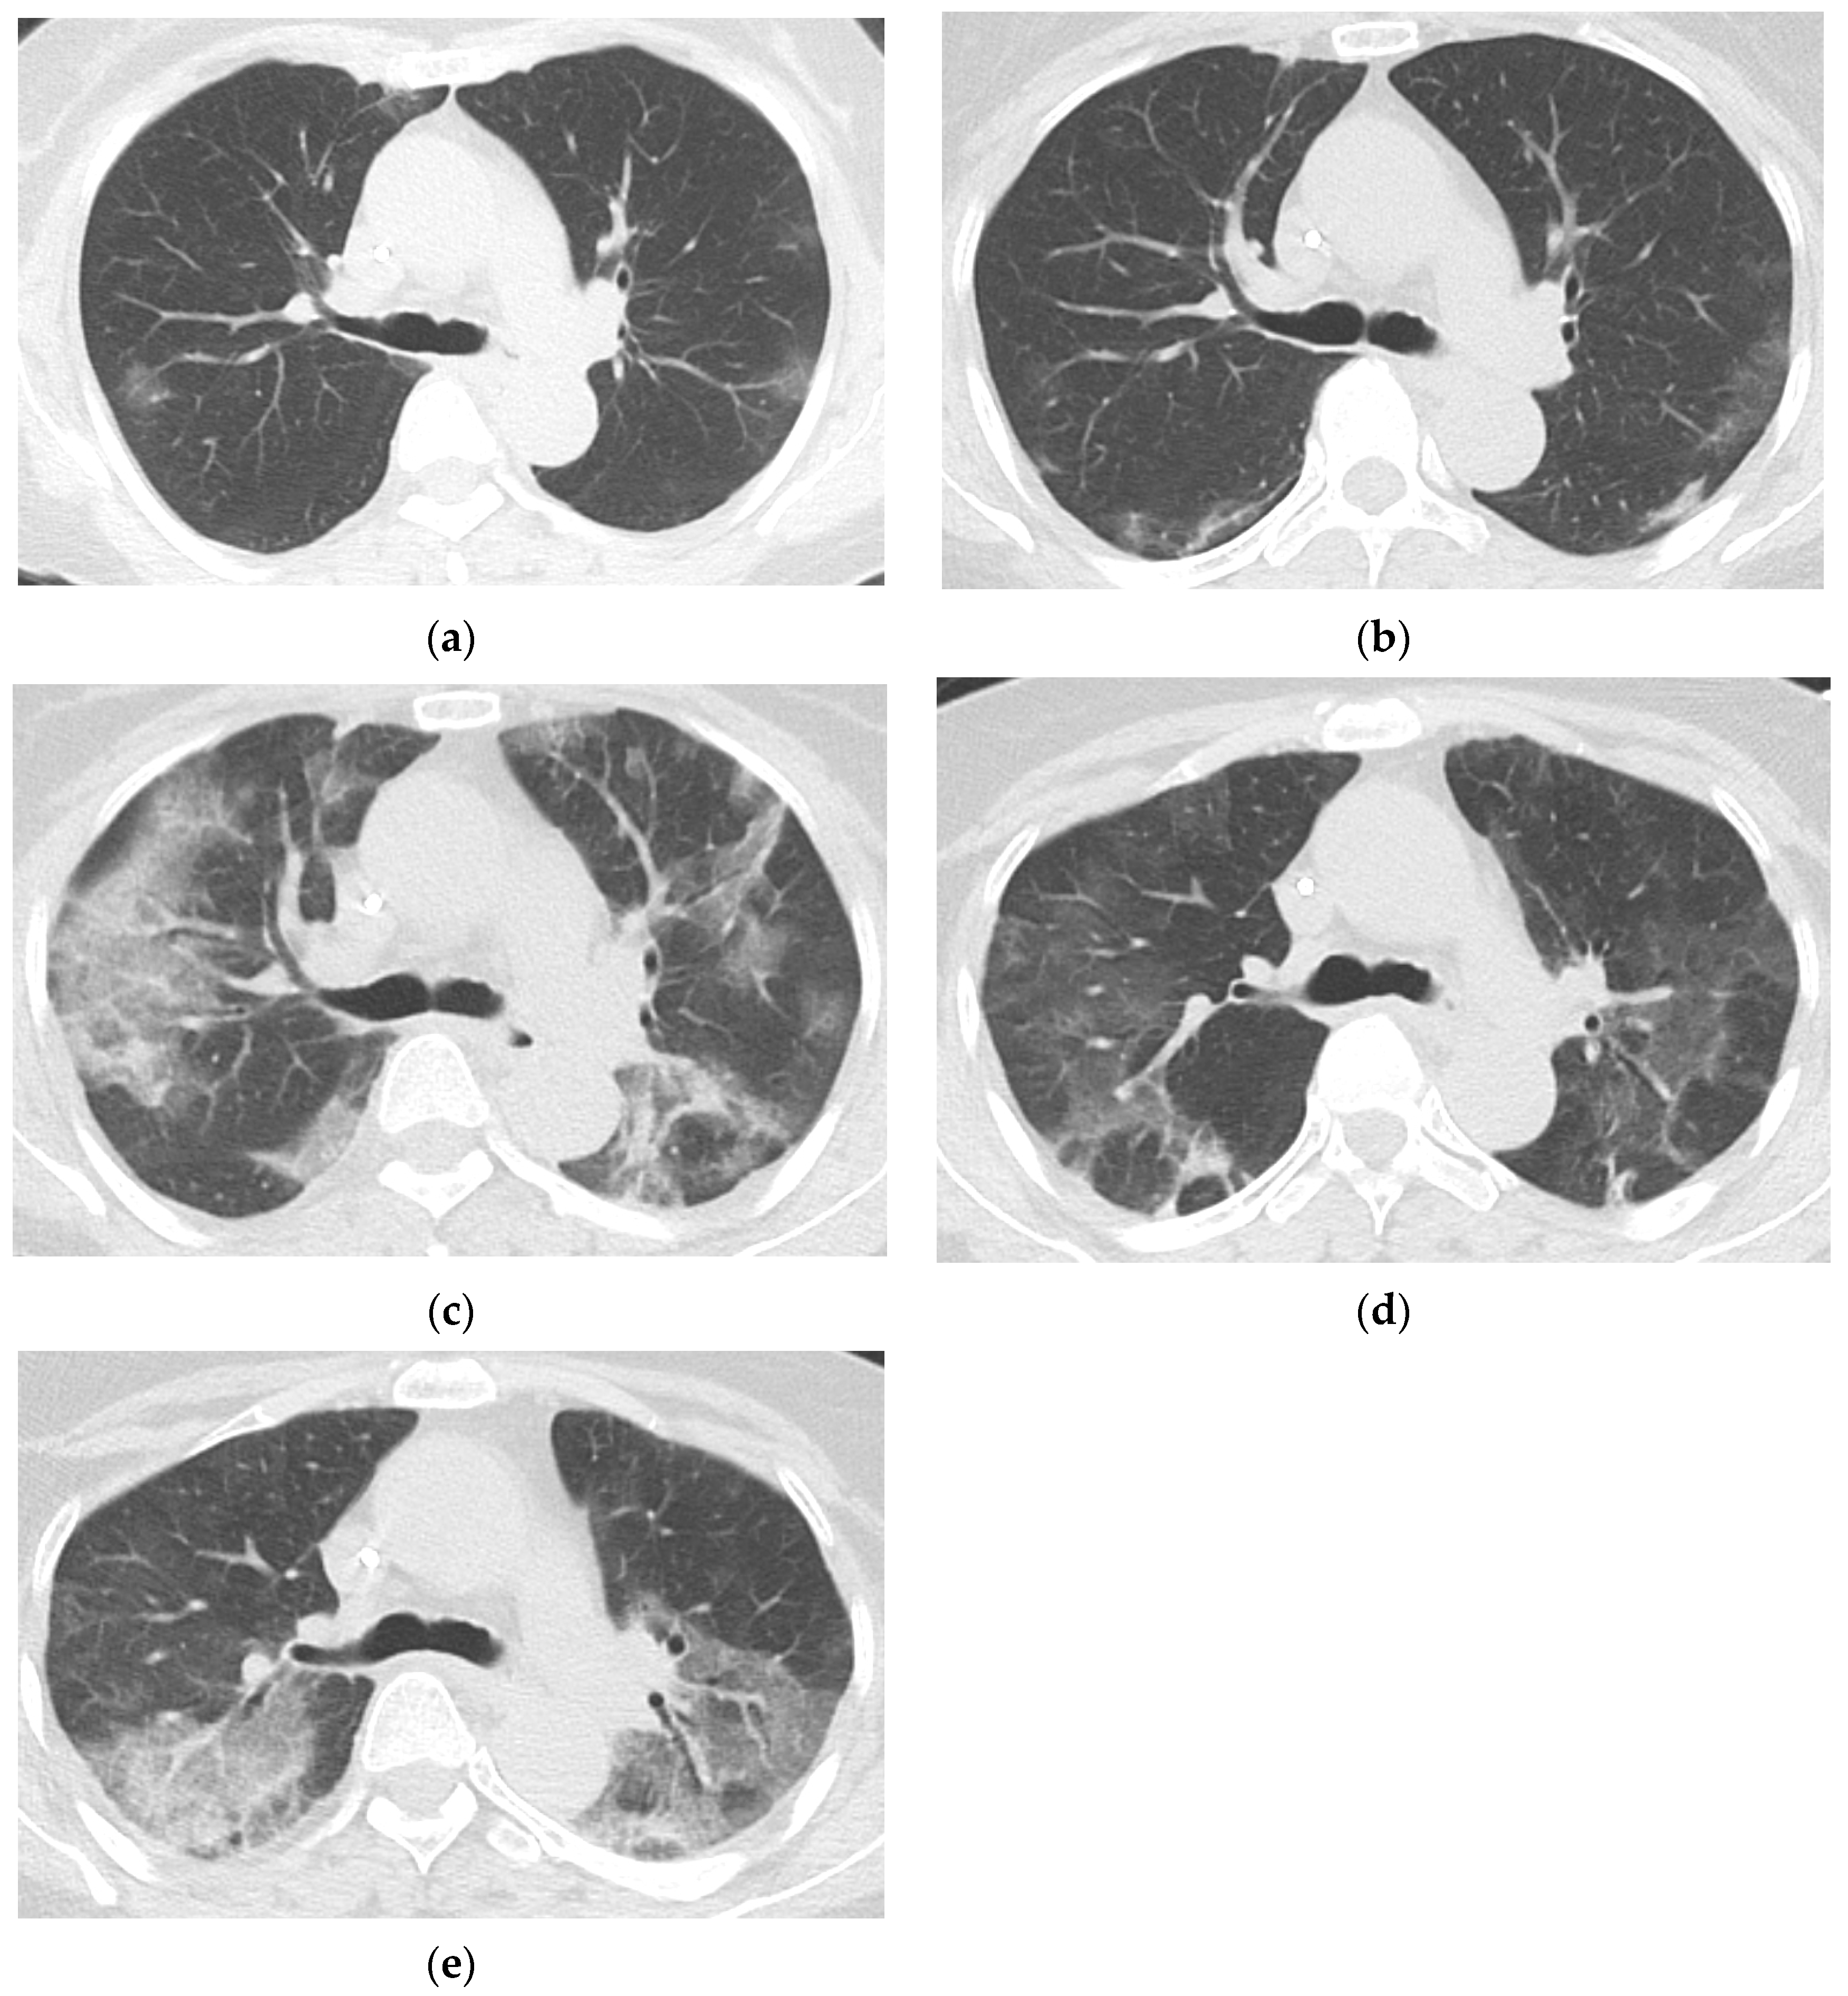

3.3. Baseline and Follow-Up Chest CT Findings

- Lee, J.; Lee, R.; Beck, K.S.; Han, D.H.; Min, G.J.; Chang, S.; Jung, J.I.; Lee, D.G. Migratory Pneumonia in Prolonged SARS-CoV-2 Infection in Patients Treated with B-cell Depletion Therapies for B-cell Lymphoma. Korean J. Radiol. 2023, 24, 362–370. [Google Scholar] [CrossRef] [PubMed]